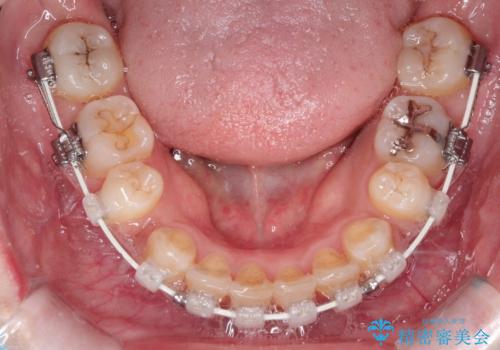

- 患者様は、歯並びのガタガタ(重度の叢生)を改善したいとのことで来院されました。診察すると、歯列のスペース不足が著しく、前歯が重なり合い、噛み合わせにも影響が出ている状態でした。歯をきれいに並べるためには抜歯によるスペース確保が不可欠と判断し、上下の小臼歯4本を抜歯したうえで、目立ちにくい審美ワイヤー矯正(白いワイヤーと透明ブラケット)を用いた治療計画を立てました。

抜歯によって歯を動かすためのスペースを確保。その後、審美ワイヤー矯正を用いて歯を1本ずつ適切な位置に誘導しながら、噛み合わせのバランスも整えていきました。時間はかかりましたが、ガタガタの歯並びがきれいに整い、機能的にも審美的にも満足のいく仕上がりとなりました。患者様からは「歯並びが劇的に改善し、見た目だけでなく噛みやすさも向上した」と喜びの声をいただきました。